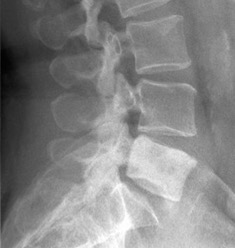

In lateral radiographs following things have to be looked for:

- Alignment

- All components of vertebrae

- Remember that the L5 foramen is projectionally small

- Intervertebral disc space

- Soft tissue

Disc space narrowing:

Differentials include:

- Infection

- Disc herniation

- Remember that the normal L4-5 disc space is greater than other intervertebral disc spaces